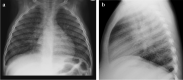

Tuberculosis (TB) remains one of the major public health threats worldwide, despite improved diagnostic and therapeutic methods. Tuberculosis is one of the main causes of infectious disease in the chest and is associated with substantial morbidity and mortality in paediatric populations, particularly in low- and middle-income countries. Due to the difficulty in obtaining microbiological confirmation of pulmonary TB in children, diagnosis often relies on a combination of clinical and radiological findings. The early diagnosis of central nervous system TB is challenging with presumptive diagnosis heavily reliant on imaging. Brain infection can present as a diffuse exudative basal leptomeningitis or as localised disease (tuberculoma, abscess, cerebritis). Spinal TB may present as radiculomyelitis, spinal tuberculoma or abscess or epidural phlegmon. Musculoskeletal manifestation accounts for 10% of extrapulmonary presentations but is easily overlooked with its insidious clinical course and non-specific imaging findings. Common musculoskeletal manifestations of TB include spondylitis, arthritis and osteomyelitis, while tenosynovitis and bursitis are less common. Abdominal TB presents with a triad of pain, fever and weight loss. Abdominal TB may occur in various forms, as tuberculous lymphadenopathy or peritoneal, gastrointestinal or visceral TB. Chest radiographs should be performed, as approximately 15% to 25% of children with abdominal TB have concomitant pulmonary infection. Urogenital TB is rare in children. This article will review the classic radiological findings in childhood TB in each of the major systems in order of clinical prevalence, namely chest, central nervous system, spine, musculoskeletal, abdomen and genitourinary system.